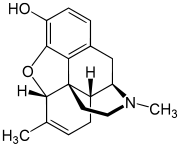

Dihydrocodeine series

Others

- 1-Nitroaknadinine * 14-episinomenine

- 5,6-Dihydronorsalutaridine

- 6-Keto Nalbuphine

- Aknadinine

- Butorphanol

- Cephakicine

- Cephasamine

- Cyprodime

- Drotebanol

- Fenfangjine G

- Ketorfanol

- Nalbuphine

- Nalbuphone

- Tannagine

Structures

| Other Morphinans | ||||

|---|---|---|---|---|

1-Nitroaknadinine 1-Nitroaknadinine |

14-episinomenine 14-episinomenine |

5,6-Dihydronorsalutaridine 5,6-Dihydronorsalutaridine |

6-Keto Nalbuphine 6-Keto Nalbuphine |

Aknadinine Aknadinine |

Butorphanol Butorphanol |

Cephakicine Cephakicine |

Cephasamine Cephasamine |

Cyprodime Cyprodime |

Drotebanol Drotebanol |

Fenfangjine G Fenfangjine G |

Nalbuphine Nalbuphine |

Sinococuline Sinococuline |

Sinomenine Sinomenine |

Tannagine Tannagine |